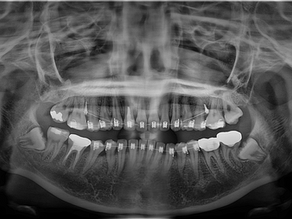

연산동사랑니치과 교정 종료 후, 충치치료 및 사랑니 발치를 한 치료사례